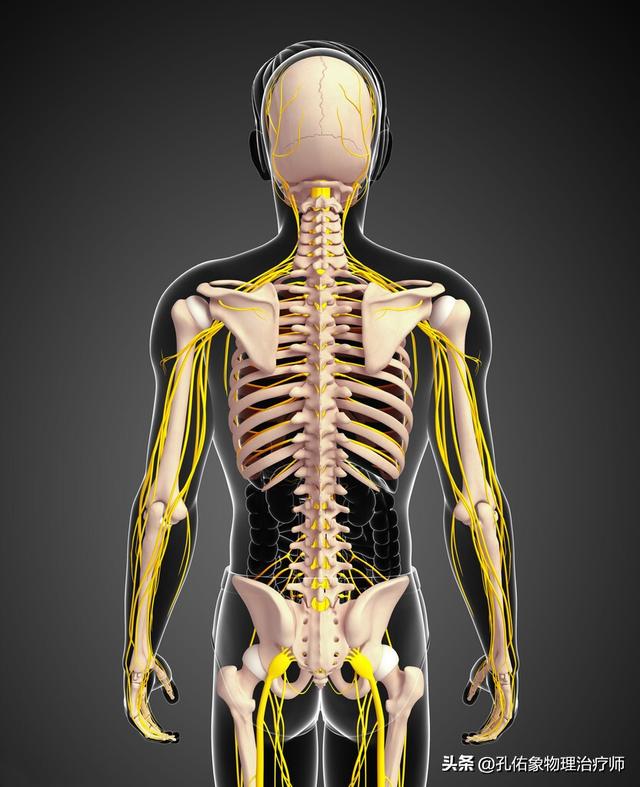

En résumé, tous ces groupes musculaires font partie de l'appareil locomoteur.Innervation des racines nerveuses C5-8 et T1-2L'étendue de la douleur irradiée correspond également à l'étendue de l'innervation des branches antérieures de ces nerfs. Par conséquent.L'épaule gelée peut également être un type particulier de spondylose cervicale.。

Les zones fréquemment douloureuses ou les muscles affectés sont le deltoïde, le pectoral mineur, l'infra-épineux, le supra-épineux, le vaste latéral, le latissimus dorsi, le biceps et la bourse de la coiffe des rotateurs.Les points de pression se situent principalement au niveau des attaches os-tendon.或Sur les points sensibles des nerfs innervant ces muscles, on peut sentir à la palpation qu'ils sont striés et indurés.